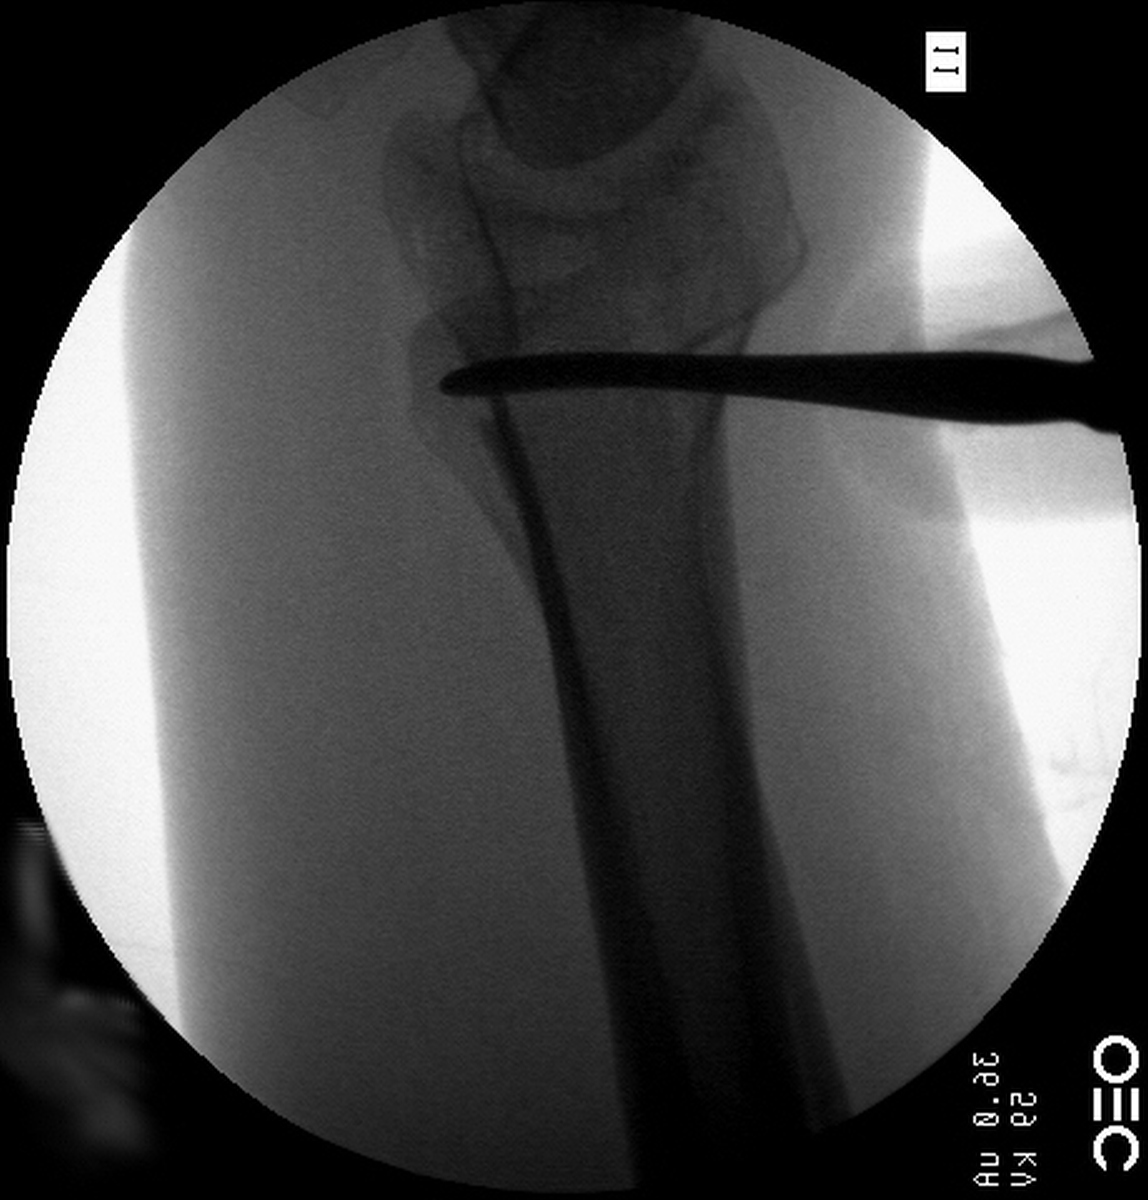

| Case 6 Extraarticular distal radius fracture with angulation and dorsal comminution. |

| Attempts at

closed reduction alone were unsuccessful. |

| Freer elevator

introduced percutaneously as a reduction aid. |

| Percutaneous

fracture stabilization with three pins via the

dorsal radial tubercle, radial styloid and FCR

portals. |